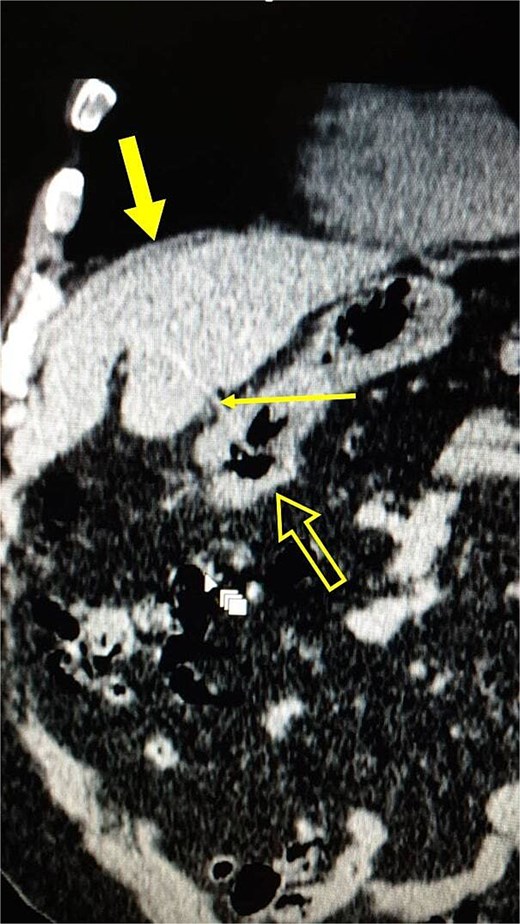

A non-contrast computed tomography (CT) scan was performed, confirming the ultrasound findings and revealing a hyperdense linear structure measuring 6 cm, penetrating the stomach and extending to the left liver lobe, with no evidence of free air or signs of bowel perforation (Fig. 2).

Coronal section of a non-contrast CT scan of the abdomen, showing a hyperdense linear structure (thin arrow) penetrating the stomach (not-filled arrow) and extending into the left liver lobe (thick arrow).